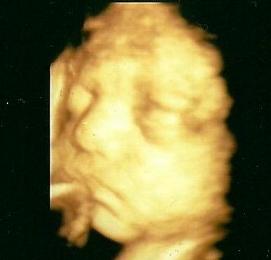

Nonó az elsőn,Bazsi a másodikon:

Kép Kép